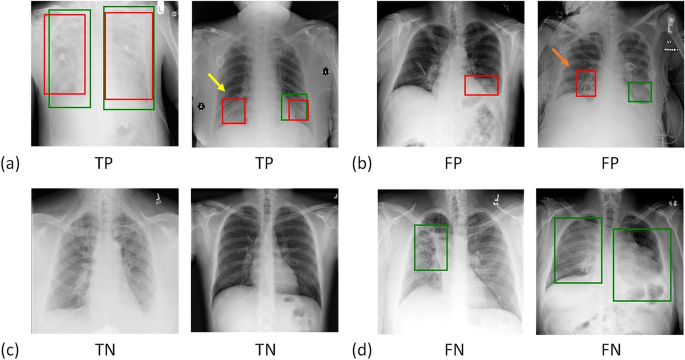

Figure 4 illustrates examples of the predicted results from the CXR test set. Figures 4a and b demonstrate positive and negative predictions, respectively. The region of lung opacity of true and predicted labels are denoted by the green and red bounding boxes, respectively. In Fig. 4a, all CXR images exhibit red boxes, indicating classification as positive cases by the UNet model. The first two cases were classified as true-positive (TP) observations, and the last two cases were identified as false positive (FP) observations. Only when the green and red boxes overlapped did we designate a TP observation. For the second case, the predicted and true findings were both positive, and the green and red boxes overlapped. Although the model also generated an FP red box (indicated by the yellow arrow), we classified this prediction as a TP case. For the fourth case, although the predicted and true findings were both positive, we defined it an FP case because the predicted region (indicated by the orange arrow) did not overlap with the true region of lung opacity.

Example results of predicted cases, including (a) true positives (TP), (b) false positives (FP), (c) true negatives (TN), and (d) false negatives (FN). The true and predicted lung-opacity regions are denoted by green and red bounding boxes, respectively. Within the definitions of this study, we considered the second example in (a) to be a TP despite one of the two predicted boxes (yellow arrow) not overlapping with the reference box. We regarded the second example in (b) as an FP. Although the CXR model correctly predicted this as positive, the predicted region, indicated by the orange arrow, does not overlap with the green box.